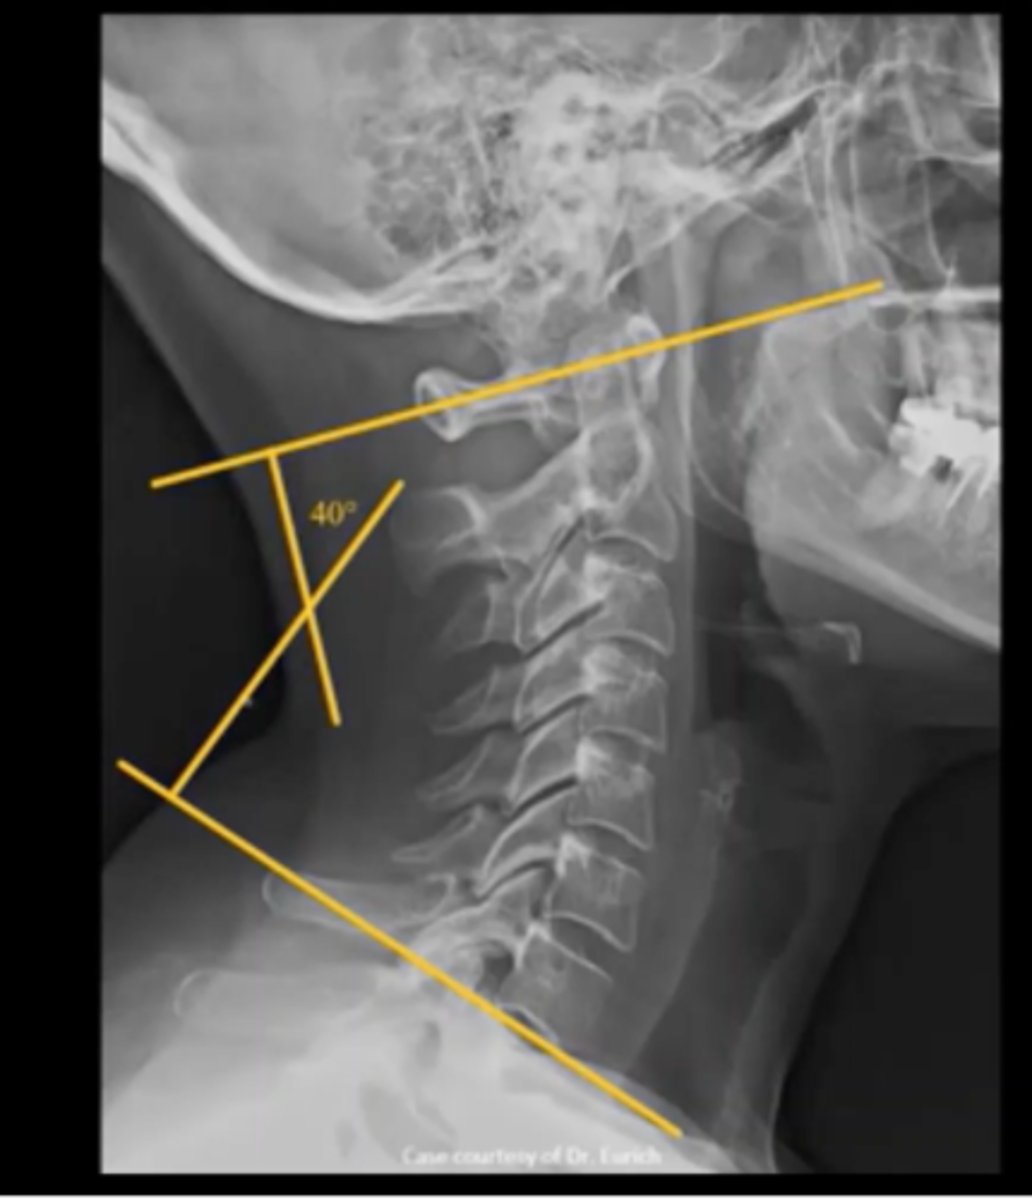

cervial lordosis (convex forwards)

thoracic kyphosis (convex backwards)

lumbar lordosis (convex forwards)

sacral kyphosis (convex backwards)